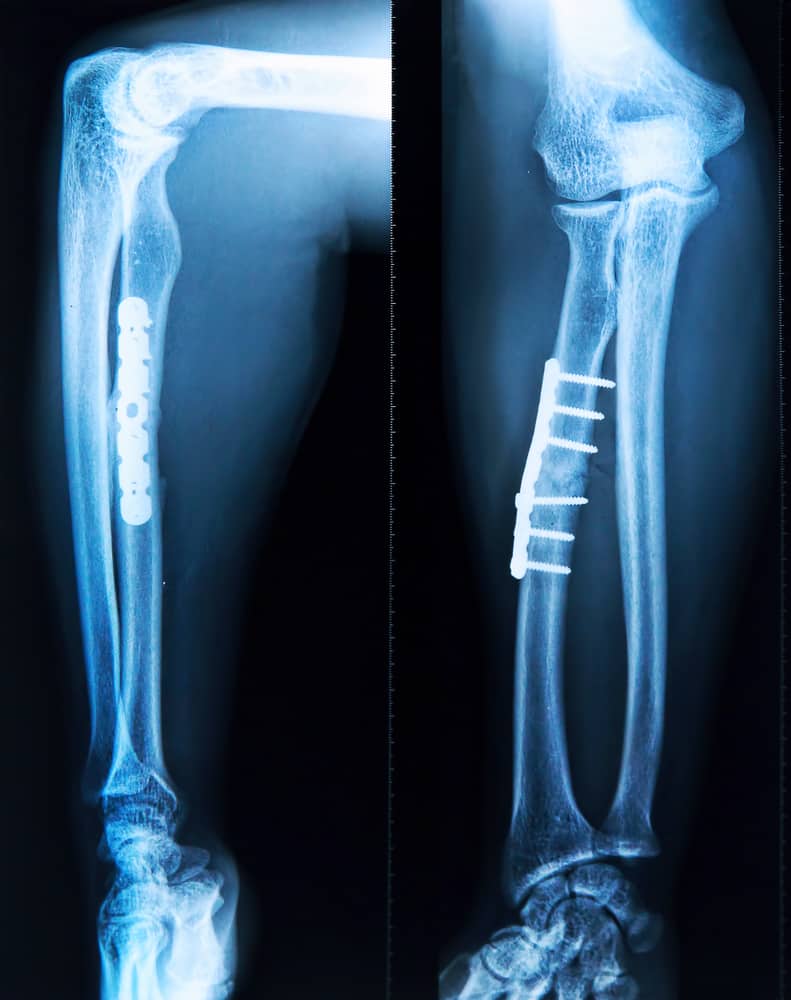

सबसे पहले डॉक्टर इस बात का निर्णय लेंगे कि पेशेंट्स के लिए कौन-सी बोन ग्राफ्टिंग सर्जरी ठीक है। पेशेंट को एनेस्थीसिया दिया जाता है। पेशेंट के बेहोश होने के बाद जिस एरिया की ग्राफ्टिंग करेंगे वहां की सर्जरी शुरू करेंगे। सर्जरी के दौरान आवश्यकता अनुसार पिन, प्लेट, स्क्रू, वायर या केबल का इस्तेमाल कर सकते हैं। इस प्रक्रिया के बाद स्टीच की जाती है।